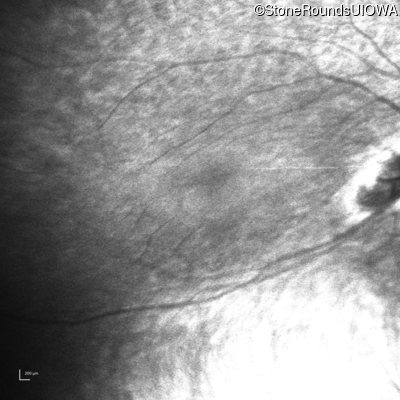

Infrared Fundus Photograph - Right - Light Perception

Exemplar